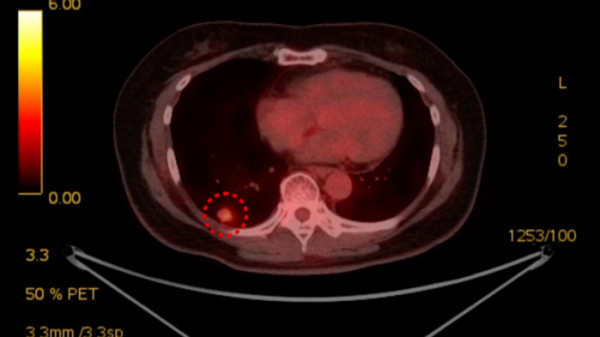

최근엔 폐암 3기 환자들에게도 새로운 치료의 길이 열리고 있다. 폐암 3기를 진단받은 64세 남성은 항암이라는 말만 들어도 두려웠다. 하지만 그가 받은 면역항암은 익히 알려진 항암과 달랐다. 항암 치료 동안 밥도 잘 먹고 머리도 안 빠졌다. 부작용은 거의 못 느꼈지만, 효과는 확실했다. 그는 4.4cm의 종양을 1.1cm로 줄였고 수술로 암을 완전히 제거했다. 57세 여성 또한 2년 반 전에 폐암 3기 진단을 받았지만, 수술을 받을 수 있었다. 그녀에게 적용된 치료법은 바로 표적치료제. 간편한 알약 형태로, 표적치료제를 매일 복용한 것만으로 종양이 줄었다. 이제는 환자 개개인 맞춤 치료가 중요한 시점. 폐암의 무서운 얼굴이 달라지고 있다.